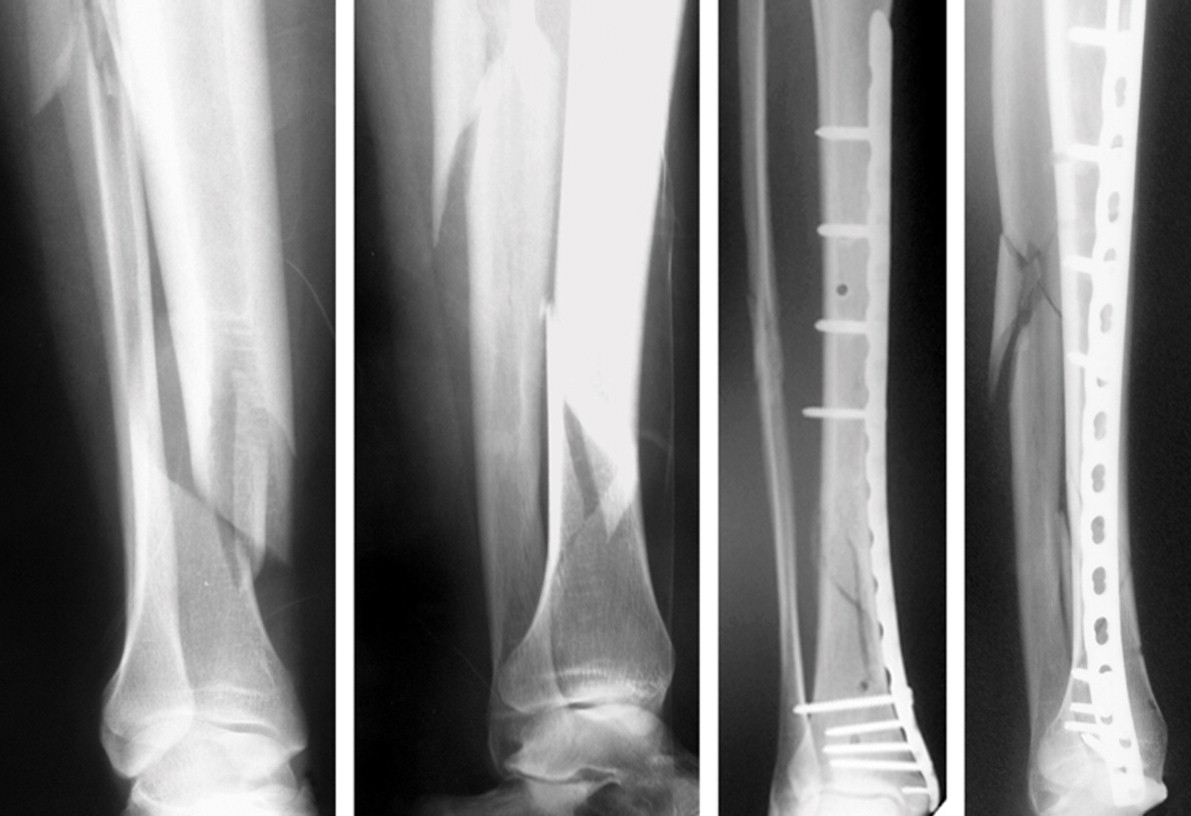

La osteosíntesis es el término que se emplea para describir la intervención mediante la cual se vuelven a alinear los fragmentos de hueso fracturado y se mantienen en posición con elementos externos metálicos. Estos pueden ser tornillos, placas o clavos.

La ostesíntesis de hoy considera además de la reducción y fijación estable de la fractura, las variables biomecánicas y la importancia fisiológica de los tejidos blandos (aquellos no óseos que se relacionan con el esqueleto).

El resultado final de una osteosíntesis debería ser la restauración anatómica y de la función de hueso comprometido mientras se cura la fractura.

La osteosíntesis abarca 3 fases, la primera es la “exposición de fractura” y luego se procede a reducir y fijar la fractura de manera temporal. Por último, se realiza la fijación definitiva y consecuencia se logra que cómo funciona la osteosíntesis sea exitosa.

Entre los recursos utilizados están los pines, alambres, agujas, clavos, tornillos y placas. Estos están fabricados con polímeros bioabsorbibles y aleaciones de titanio.